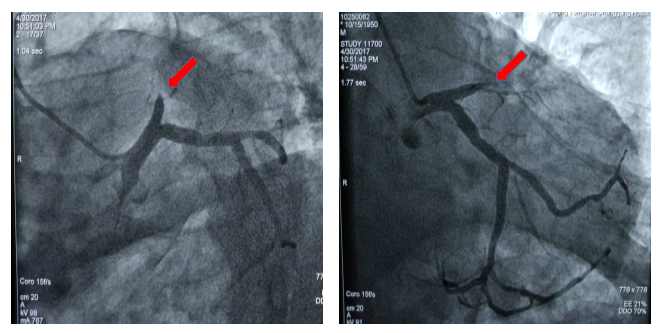

图2 患者术后冠脉造影显示冠脉血管前降支支架治疗后完全开通